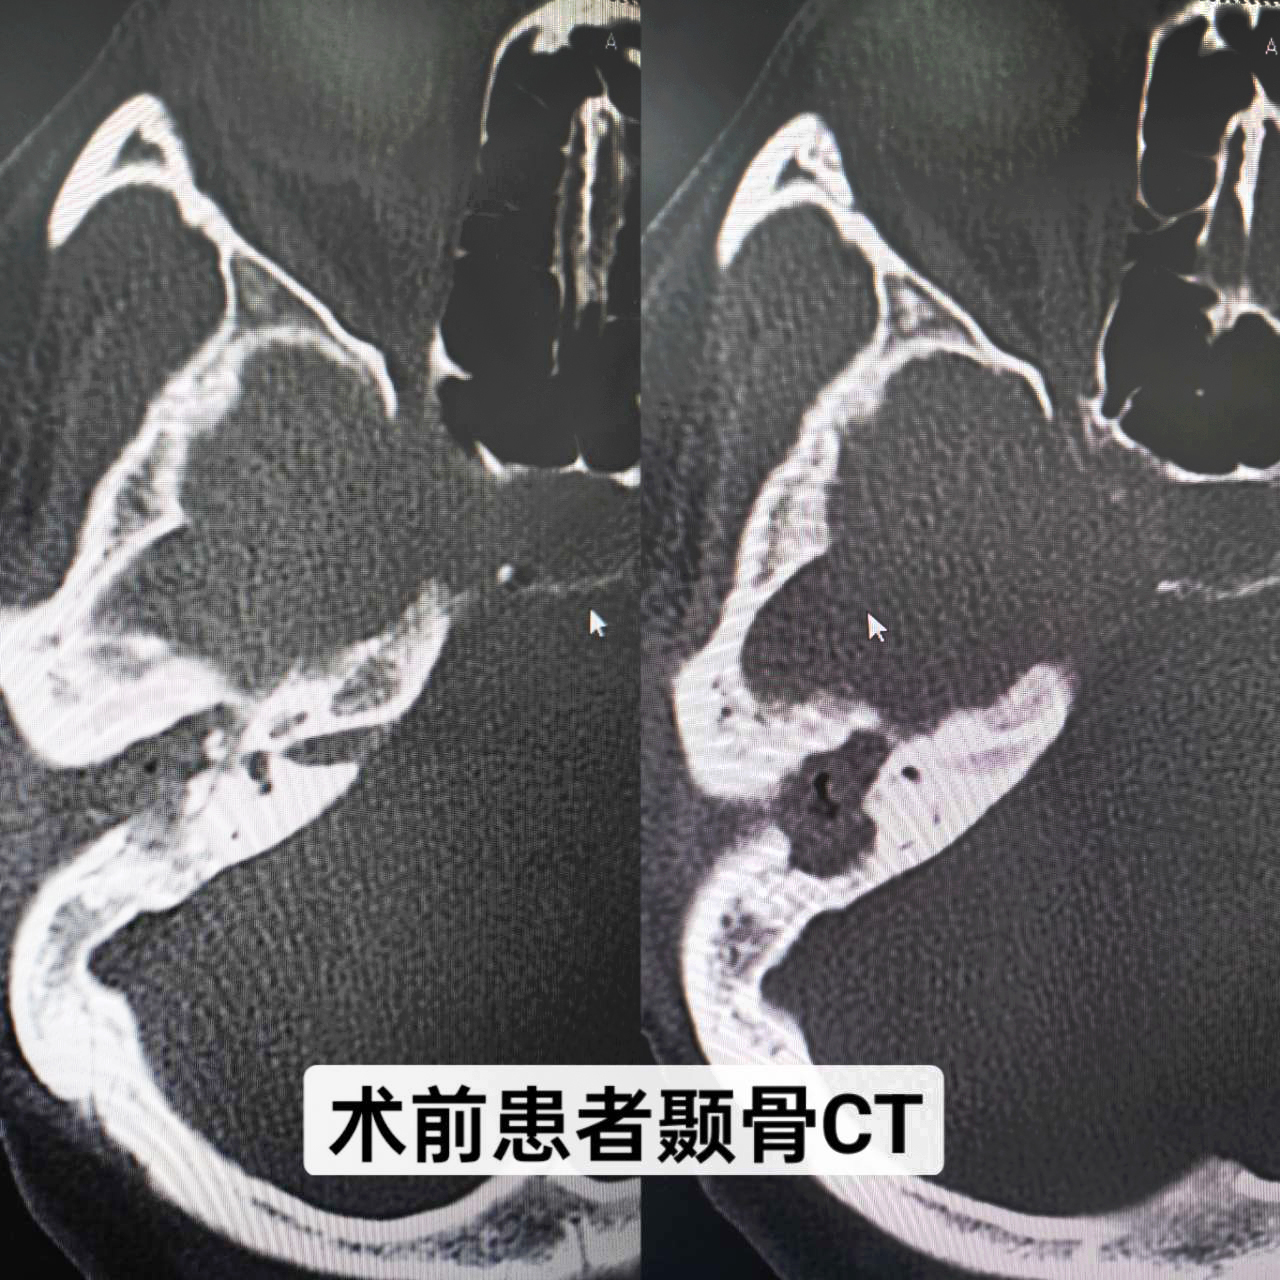

患者,女,34歲,幼兒時發生過中耳炎,經治療后已明顯好轉,但最近一個月反復右耳腫痛、流膿、流水,伴聽力下降,嚴重影響生活,來我院就診。耳內鏡示:右耳外耳道縮窄,肉芽組織及膿血性分泌物填充,鼓膜窺不及;顳骨CT示:右側中耳鼓室擴大,見軟組織影填充并向外耳道延伸,右側聽小骨骨質吸收,形態小,部分聽骨欠清,考慮:右側膽脂瘤型中耳炎(累及右側外耳道)。耳鼻咽喉科副主任顏抗經過閱片及結合患者病史,判斷患者是中耳膽脂瘤造成聽小骨斷裂,建議患者入院手術治療。